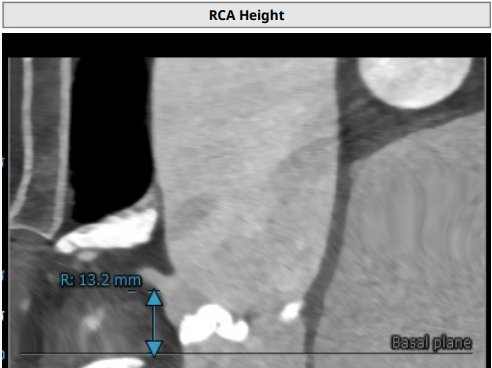

左冠高度7.1mm, 右冠高度13.2mm.

患者为TYPE1型二叶瓣,重度钙化,左右可见钙化脊,左冠高度低,可能存在较高的冠脉风险,该患者对于瓣膜释放位置要求较高,容错空间很小,法式窦结构可,需要在术中球囊扩张时着重观察冠脉即刻情况且做出相应判断。左室大小可,升主动脉未见明显扩张,心脏角度43°。